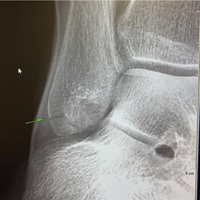

折れていました

朝さんぽで足を捻ったよっぴ〜あまりにも痛いので病院へ捻挫と思っていたら くるぶしの骨にヒビが。。。😭😭😭全治3ヶ月ではおいしいごはんも朝さんぽもしばらくおあずけブログの更新がゆっくりになると思いますすみません🙇♀️ ランキング参加中ライフスタイル ランキング参加中gooからきました